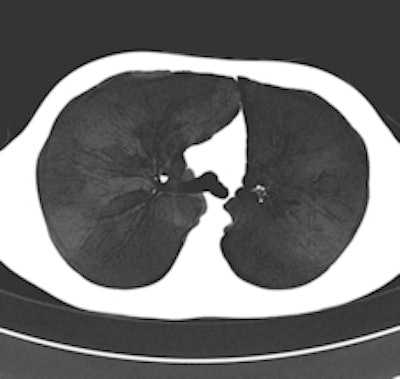

Maximum intensity projection (MIP, left) and minimum intensity projection (MinIP, right) images were calculated on demand by 24 (49%) and 20 (41%), respectively, of the survey's respondents. MIPs are particularly helpful in detecting small pulmonary nodules and determining the distribution of the nodules. MinIPs are used to ease the detection and quantification of subtle emphysema. All images provided by Dr. Helmut Prosch."The message we want to send is that state-of-the art CT protocols should include volume datasets with dose modulation switched on and the tube potential adjusted to the age and size of the patient," Prosch added. "While many radiologists use dose modulation tools, not all define the kVp depending on the patient."

Chest CT with activated automatic dose modulation. Automatic dose modulation reduces the radiation dose by adjusting the dose along the patient's length axis. Dose modulation allows a dose reduction of up to 30%.The risk of radiation-induced cancer is real but its extent is not yet fully understood, given that current thinking is based mainly on data extrapolated from Hiroshima and that it remains hard to discern radiation-induced cancer from that which is nonradiation induced, he explained. Because CT answers a lot of questions that simple chest x-ray can't, and because treatment depends on these CT results, the modality is being increasingly used, and radiation dose to the whole population is growing year by year.